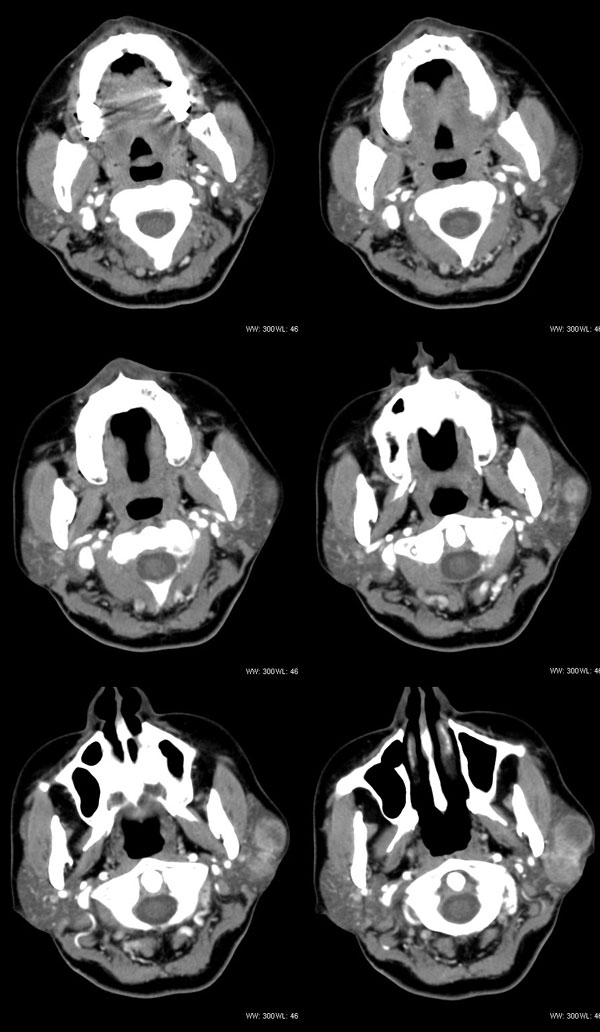

女性,43岁。左腮部肿物5年。体检:(肿物)质中,约5x4x4cm,边界清,固定。

左腮腺肿物,内可见低密度坏死区,增强扫描示肿块明显强化,且呈持续延迟强化,常规考虑腮混合瘤可能性大,但强化表现不太符合,不除外腮腺纤维血管瘤、神经鞘瘤、淋巴瘤及巨淋巴结增生症

考虑左侧腮腺混合瘤。  肿瘤较大,边清,囊变,强化明显,皮肤及淋巴结无异示

左侧腮腺多形性腺瘤可能性大。1、是混合瘤中最常见的良性肿瘤;2、中年女性多见并且时间长症状轻;3、病灶内有低密度坏死区,增强时强化;4、其内有钙化,囊性部分未强化;5、需与囊性淋巴瘤相鉴别。